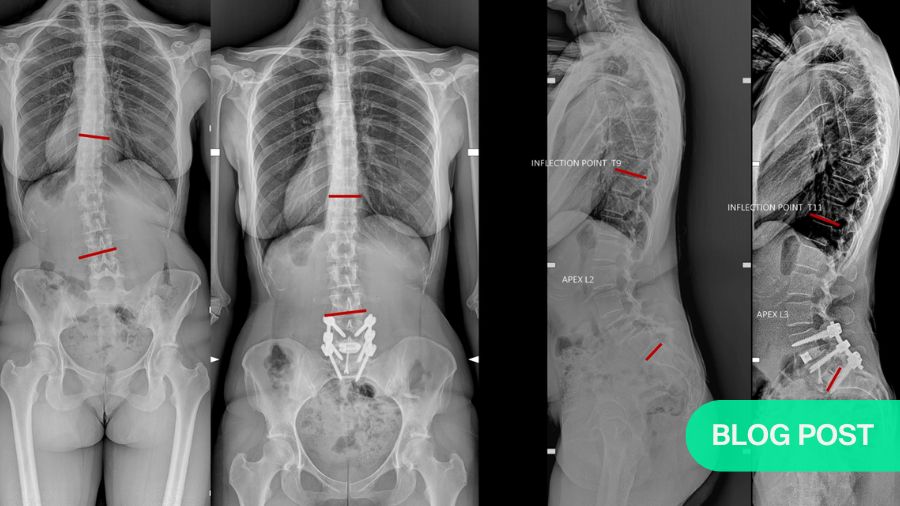

Standard radiographs demonstrated a degenerative spondylolisthesis at L4–5. Two decades ago, such a finding, especially when combined with correlating symptoms, would often have been enough to proceed directly to surgery, typically after confirming stenosis on MRI. Today, that approach is no longer considered sufficient for many patients.

More importantly, a full spine standing radiograph from C2 to the proximal femur was obtained in a standardized, relaxed position. This provided the basis for sagittal alignment analysis. Among all measured parameters, two stood out as particularly relevant:

In this patient, the pelvic incidence measured approximately 75°, placing her at the very high end of the spectrum. High PI fundamentally increases the biomechanical demand on the lumbar spine.

Several compensatory strategies were evident:

- Pelvic retroversion, reflected by an increased pelvic tilt, indicating that the patient was rotating her pelvis posteriorly to compensate for the lack of lumbar lordosis.

- Hyperextension at L3–4, the disc above the spondylolisthesis, suggesting that adjacent segments were being driven into excessive motion to maintain global balance.

- Thoracic straightening and extension, with proximal migration of the kyphosis–lordosis inflection point to around T9–T10.

While these compensations allow the patient to remain upright, they come at a cost. Compensation requires continuous muscular activation. Over time, this contributes to fatigue, pain, and further mechanical overload of adjacent discs and facet joints. Although definitive proof that such compensation directly accelerates adjacent segment degeneration is limited, the clinical association is strong and familiar to most spine surgeons.

Postoperative imaging demonstrated restoration of alignment and stable fixation from L4 to S1. However, what was particularly striking was the effect on the non-fused segments:

- The compensatory hyperlordosis at L3–4 decreased.

- Thoracic extension was reduced.

- The inflection point between thoracic kyphosis and lumbar lordosis migrated caudally.

These indirect changes illustrate a key concept of modern alignment surgery: successful correction allows the spine to abandon compensation. Compensation, while initially protective, is ultimately exhausting and mechanically costly. Removing the need for compensation may be as important as correcting the index pathology itself.